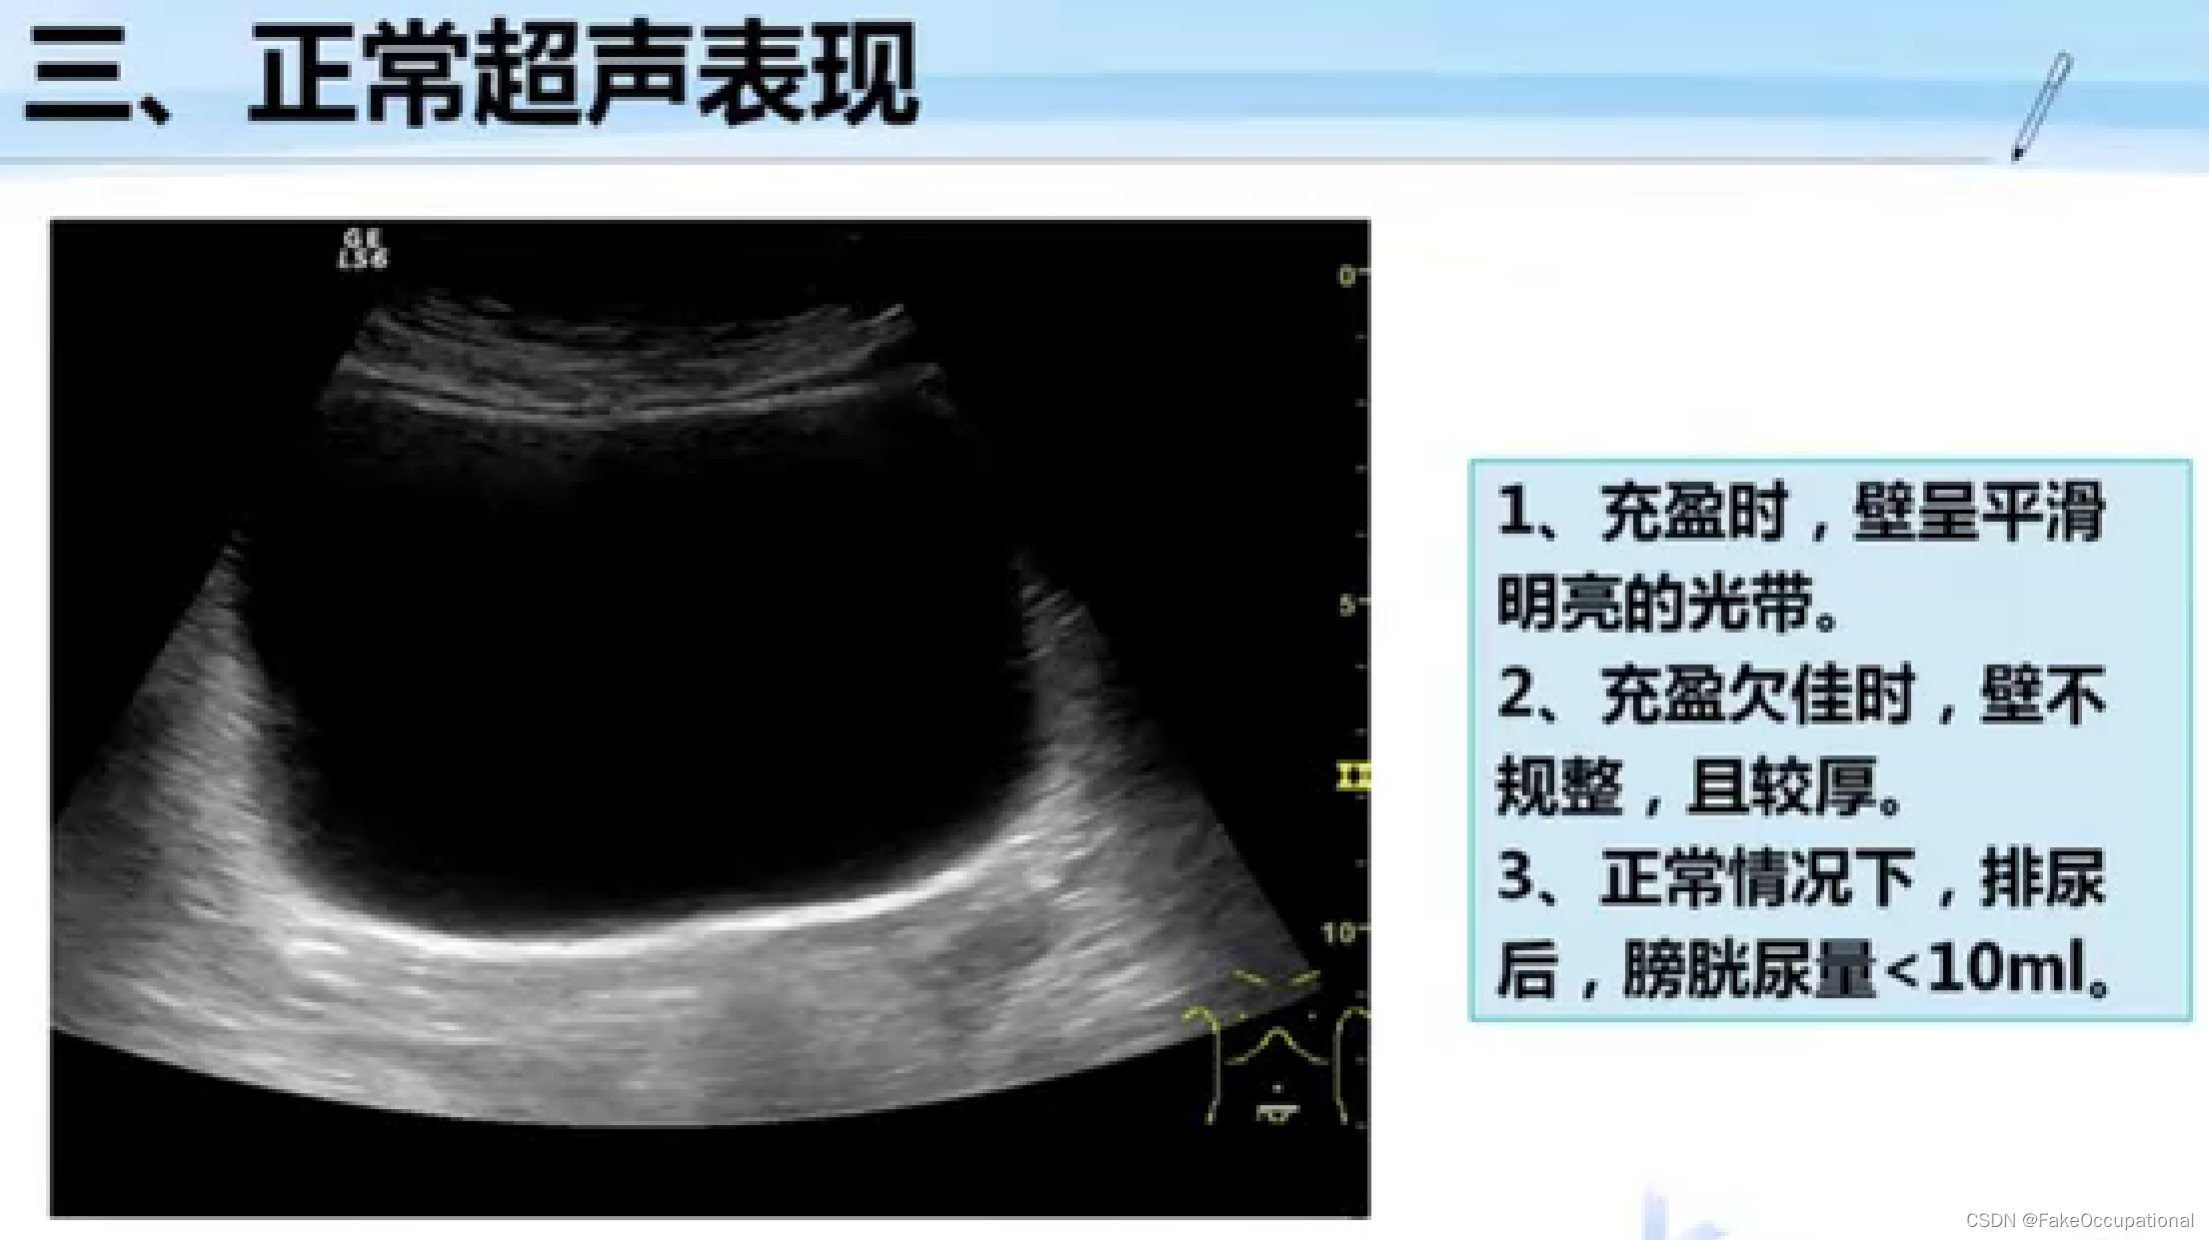

膀胱超声

1、检查前准备

检查前40分钟饮水500ml充盈膀胱,直至有尿意

2、探测方法

经腹壁探查:仰卧位,探头放置耻骨上。经直肠检查:排便或灌肠一次少量尿液即可,取膝胸位、截石位或左侧卧位,探头插入肛门。